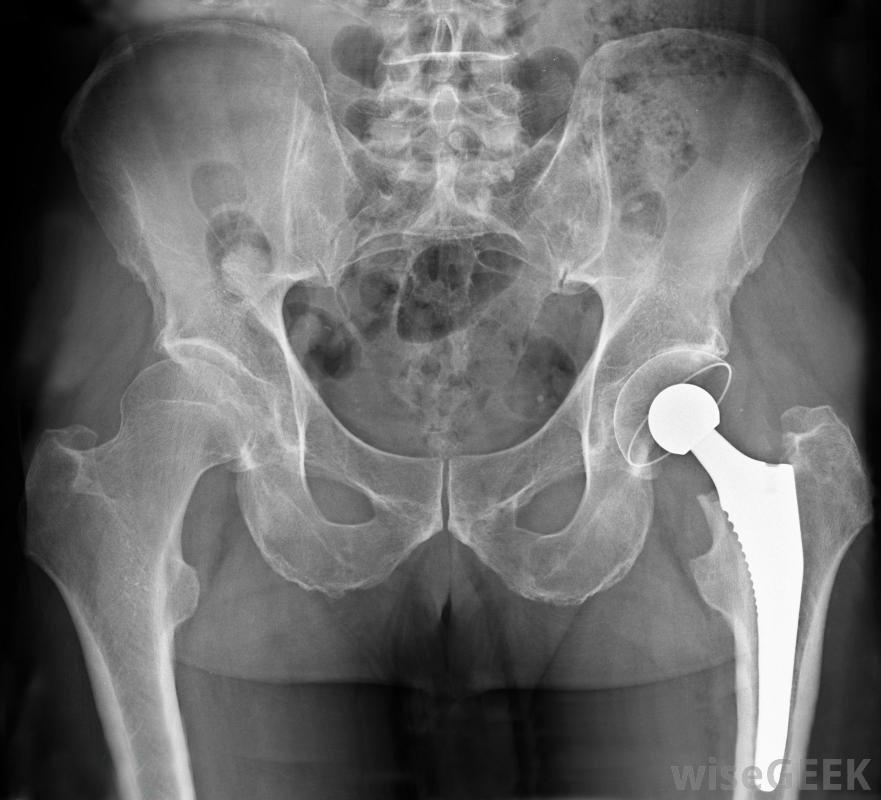

人工關節是一種治療設備。

許多不同類型的治療設備用于那些身體有缺陷、不能行走的人。拐杖和拐杖可以幫助他們那些有暫時或輕微損傷的人,而那些有更嚴重限制的人可以使用步行機和輪椅人工關節可以替代患者受損的現有關節,以提供更好的整體活動能力。最常見的手術包括膝關節或髖關節置換。物理治療設備,包括按摩臺、舉重機,甚至是熱水浴缸,可用于幫助患者在手術或事故后恢復活動能力。